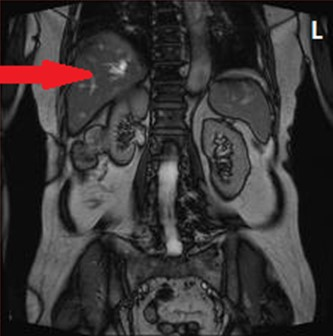

Którą strukturę anatomiczną uwidoczniono na zamieszczonym obrazie USG?

Ilustracja do pytania 5

A. Pęcherzyk żółciowy z kamieniami.

B. Ciężarną macicę z czterema płodami.

C. Nerkę lewą ze złogami.

D. Pęcherz moczowy z kamieniami.